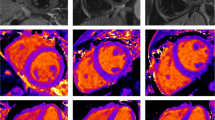

Currently, MRI plays an important role in assessing global or regional dysfunction and structural alternations of the heart in patients suspected of ARVC/D. MRI also has the ability to visualize fibrosis of the myocardium with delayed enhancement inversion recovery (DE) imaging following intravenous injection of a gadolinium contrast agent [10, 11]. The contrast diffuses into the myocardial extracellular space, which is larger in fibrotic myocardium and therefore remains longer in the fibrotic tissue than in healthy myocardium [12]. The gadolinium within the extracellular space can be demonstrated by T1 W gradient echo-inversion recovery (IR) imaging (Fig. 1). The inversion time is chosen to null the signal of the normal myocardium and thereby improve visibility of delayed enhancement in the abnormal myocardium. Although delayed enhancement is not part of the diagnostic criteria for ARVC/D, it can be an important contributor in diagnostics and could guide electrophysiological examination and biopsy [13].

Examples of different image quality of the RV inferior wall (segment 29) are shown in Fig. 3.

Image quality grading results of all segments per sequence type are shown in Fig. 4. Image quality was considered to be good in 24% of all segments in the 3D group (65/270), 66% in the 2D group (211/320) and in 79% (300/380) in the PSIR group. Image quality was poor in 51% (138/270) of the segments in the 3D group, 10% (31/320) of segments in the 2D group and 2% (6/380) of segments in the PSIR group.

The image quality per segment per type of sequence is shown in Figs. 7, 8 and 9. In the 3D sequence group the anterior RV wall (segments 21, 24, 27) and the lateral RV wall (segments 25 and 28) show the highest percentages of poor image quality (Fig. 7). Consistent scores were seen over all segments in the 2D group (Fig. 8), with the lowest percentage of good image quality (53%) in the anterior RV wall (segment 24). The PSIR group had a high average score of good image quality per segment (Fig. 9). Segments 24 and 27 of the RV anterior wall showed a lower percentage of segments with a good image quality (61 and 63% respectively).